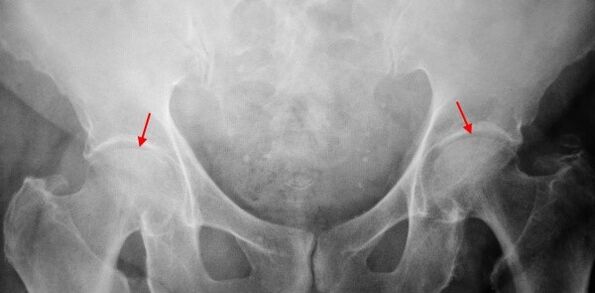

Op de X -Ray van de patiënt die lijdt aan coxarthrose van de 1e graad, worden milde veranderingen bepaald: matige ongelijke vernauwing van de gewrichtspleet, evenals botgroei rond de externe of interne rand van het acetabulum in afwezigheid van veranderingen uit het hoofd en de nek van het dijbeen.

In X -Ray -afbeeldingen voor coxarthrose van de 2e graad wordt een significante ongelijke vernauwing van de gewrichtspleet (meer dan de helft van de normale hoogte) bepaald. De femorale kop is enigszins omhoog verschoven, vervormd en neemt in grootte toe en de contouren worden ongelijk. Botgroei met deze mate van coxarthrose verschijnt niet alleen op de interne, maar ook aan de buitenrand van het acetabulum en gaan buiten het kraakbeen.

Op röntgenfoto's voor coxarthrose van de 3e graad, een scherpe vernauwing van de gewrichtspleet, worden een uitgesproken uitbreiding van de dijkop en meerdere botgroei gedetecteerd.

De diagnose van coxarthrose is gebaseerd op klinische tekenen en gegevens van aanvullende studies, waarvan de belangrijkste radiografie is. In veel gevallen maken x -reeks het mogelijk om niet alleen de mate van coxarthrose vast te stellen, maar ook de oorzaak van het optreden ervan. Dus bijvoorbeeld, een toename van de nek-diaphysphysale hoek, de scènes en afvlakking van het acetabulum duiden op dysplasie, en veranderingen in de vorm van het proximale deel van het dijbeen zijn aangegeven dat coksartrose een consequentie is van de ziekte van Perentes of jeugdige epifysiolyse. Op röntgenfoto's van patiënten met coxarthrose kunnen ook veranderingen worden gedetecteerd die letsel aangeven.